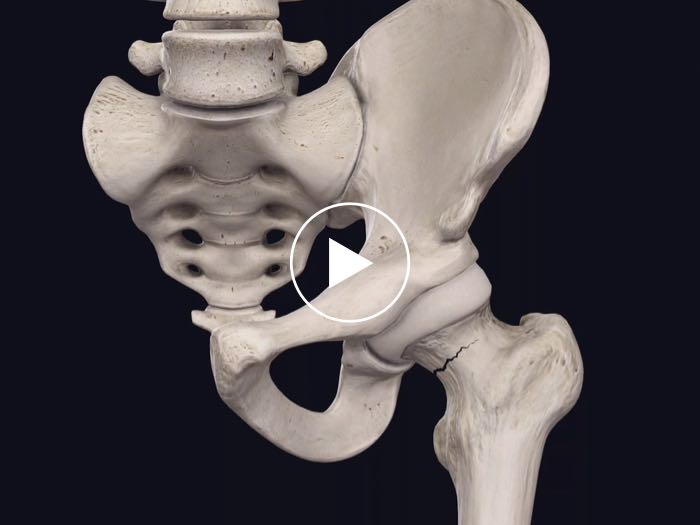

Fracture

Model injuries and conditions by cutting bones in the style of a fracture.